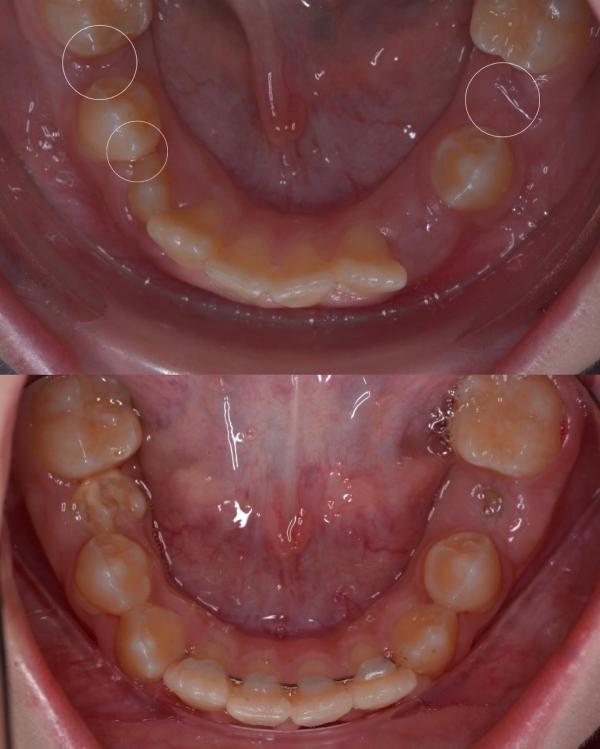

Перевоплощение длиной в 3 года …

Лечение , которое можно было бы избежать…💔

Итак , вернёмся в начало. 🖌

К этой пациентке я прониклась особенной любовью с первого визита ❤️☀️, солнечную девочку зовут Насиба, ей было на тот момент 9 лет

Пришёл ребёнок на консультацию, вижу множество проблем:

🦔Сужение верхней челюсти

🦔Дефицит места для прорезывания зубов

🦔Глубокий травматический прикус

🦔Рецесс...